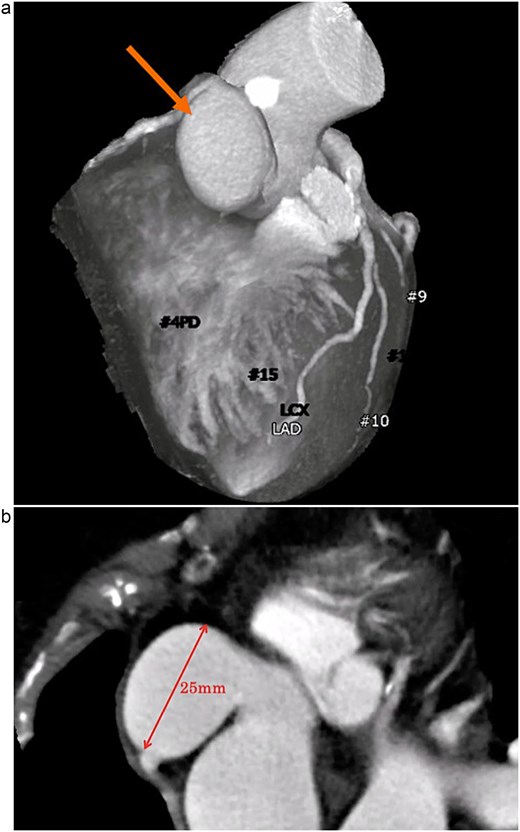

A 72-year-old woman with hypertension and dyslipidemia presented with progressive dyspnea. There was no family history of congenital heart disease. Electrocardiography showed sinus rhythm at 67 bpm and complete right bundle branch block. Contrast-enhanced computed tomography (CT) revealed a 25-mm saccular aneurysmal dilation arising from the right coronary sinus of Valsalva, without significant coronary artery stenosis (Fig. 1a and b). Transthoracic echocardiography (TTE) revealed severe AR (a regurgitant volume of 91 ml, an effective regurgitant orifice area of 0.54 cm2, and a maximum regurgitant velocity of 3.4 m/s). Left ventricular systolic function was preserved, with a left ventricular end-diastolic/systolic diameter of 55/38 mm, and no ventricular septal defect was detected (Fig. 2). Although unruptured, the aneurysm was giant and associated with severe, symptomatic AR; therefore, surgical intervention was indicated. Given an acceptable operative risk (preoperative European System for Cardiac Operative Risk Evaluation II, 3.48%), a modified Bentall procedure was performed.

(a) Contrast-enhanced CT demonstrating a saccular aneurysm arising from the right coronary sinus of Valsalva (arrow), without evidence of significant coronary artery disease. (b) Axial contrast-enhanced CT image showing the saccular aneurysm, with a maximal diameter of 25 mm.